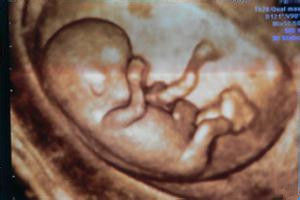

胎兒畸形1.胎兒B超

是檢查胎兒畸形的常用方法,一般在懷孕20~24周檢查,胎兒的各個臟器都已能通過B超清楚地顯現出來,如果B超發現此時胎兒嚴重畸形,就應及時流產,以免拖至妊娠晚期給孕婦造成更大的痛苦。但並不是所有的畸形胎兒都能用B超測出,因染色體異常而導致的先天愚型兒或一些微小畸形,B超就測不出來;有些畸形要到妊娠後期才能表現出來;由於超聲的解析度有限,以及技術的原因,有些畸形會在超聲檢查時漏診。